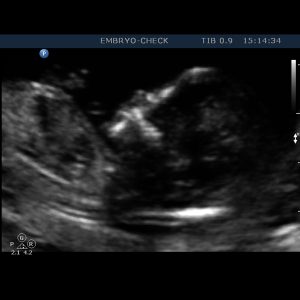

Η EMBRYOCHECK είναι εξειδικευμένη σύγχρονη μονάδα εμβρυομητρικής ιατρικής και εμβρυϊκής καρδιολογίας, αφιερωμένη στην υγεία της γυναίκας – μητέρας και του εμβρύου της και μελλοντικού παιδιού της. Ιδρύθηκε το 2006 και παρέχει υπηρεσίες που καλύπτουν όλο το φάσμα υπερηχογραφικής απεικόνισης στην μαιευτική και γυναικολογία. Βρίσκεται στο κέντρο της Αθήνας έναντι του Μεγάρου Μουσικής.